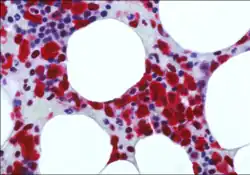

Falini's research contributions fall in the area of precision medicine. His scientific activity ranges from the field of monoclonal antibodies for diagnostic and therapeutic purposes to genomic studies on AML and hairy cell leukemia (HCL). His discoveries of NPM1 mutations in AML and BRAF-V600E in HCL, identified new mechanisms of leukemogenesis and resulted into improvement of the diagnosis, prognostic stratification, molecular monitoring and therapy of these hematological malignancies.[2]

In 2005, stemming from his immunohistological studies on ALK-positive ALCL, Falini discovered that tumor cells from about one-third of adult AML (mostly carrying a normal cytogenetic) expressed aberrantly in the cytoplasm nucleophosmin (a nucleolar located protein). This finding prompted Falini and colleagues to sequence the NPM1 gene and to discover heterozygous mutations at exon 12, responsible for the aberrant nuclear export of the NPM1 mutant protein.

Falini's group also demonstrated that NPM1 mutations are AML specific and associated with a de novo origin of the disease.[9] His research team then identified molecular variants of NPM1 mutations (other than exon 12), clarified the molecular mechanisms underlying the ectopic cytoplasmic accumulation of the NPM1 mutants[10] and proposed that it plays a critical role in leukemogenesis. Falini and colleagues also discovered a unique gene expression and microRNA profile of NPM1-mutated AML and demonstrated that over-expression of HOX genes is closely related to the cytoplasmic delocalization of NPM1 mutants.[11]